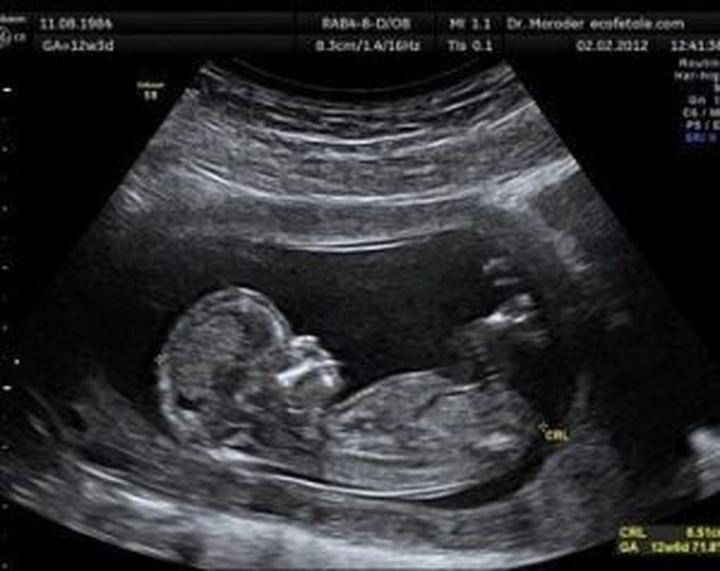

W trakcie badania lekarz stara się zmierzyć różne parametry, które stanowią cenne wskazówki dla przyszłych rodziców. Na przykład, CRL (długość ciemieniowo-siedzeniowa) to jeden z podstawowych wymiarów zarodka. Im większą wiedzę zdobędziesz, tym mniejsze prawdopodobieństwo, że później doświadczysz zaskoczenia jako „przerażony rodzic” z wynikiem USG w dłoni, na którym widnieją tajemnicze znaczki.

| CRL | Długość ciemieniowo-siedzeniowa | Podstawowy wymiar zarodka, który dostarcza informacji o jego rozwoju. |

Podczas badania USG w ciąży lekarz mierzy różne parametry, takie jak CRL (długość ciemieniowo-siedzeniowa), BPD (wymiar dwuciemieniowy główki) oraz FHR (częstość akcji serca płodu). Te dane dostarczają cennych informacji o rozwoju płodu oraz jego zdrowiu.